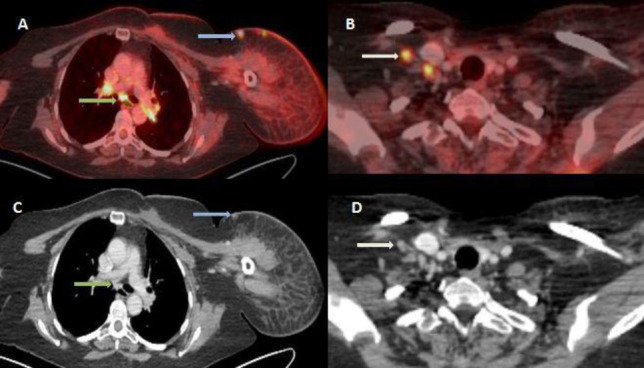

Objectives: Lymphangiosarcoma is a rare tumor that affects the upper limbs of patients who have undergone breast cancer surgery, including axillary dissection, followed by radiation therapy (RT) to the axilla and has a poor prognosis. 18F-FDG PET/CT may enable the earlier detection of malignant transformation in a setting of chronic lymphedema and help evaluate the extent and staging of the tumor, allowing earlier initiation of treatment options.

Case presentation: We herein report a case of cutaneous lymphangiosarcoma in a 47-year-old breast carcinoma patient, which occurred 9 years after initial surgery and radiation therapy. Distant metastases were detected on 18F-FDG PET/CT. The patient underwent fore-quarter amputation of the upper limb and concurrent chemo-radiation therapy. However, she succumbed to her disease after 3 cycles of chemotherapy.

Conclusions: 18F-FDG PET/CT scan helps in the early detection of malignant transformation and lymphangiosarcoma in a setting of chronic lymphedema in breast carcinoma patients following radiation therapy to the axilla. Furthermore, it helps determine the extent of regional spread and detect metastatic involvement, thus enabling better clinical management of these patients.